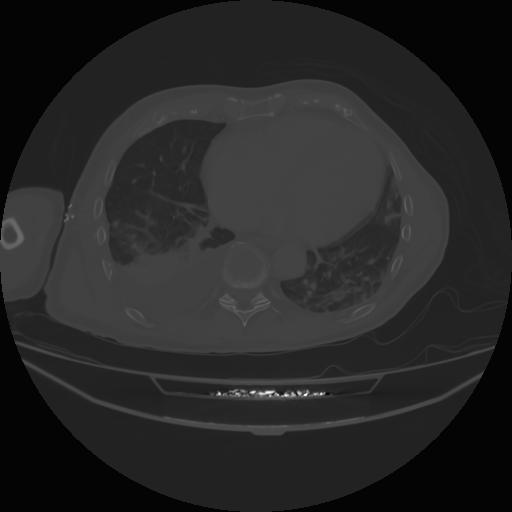

4 CUERPO,CE,Axial,3.0,CUERPO,,